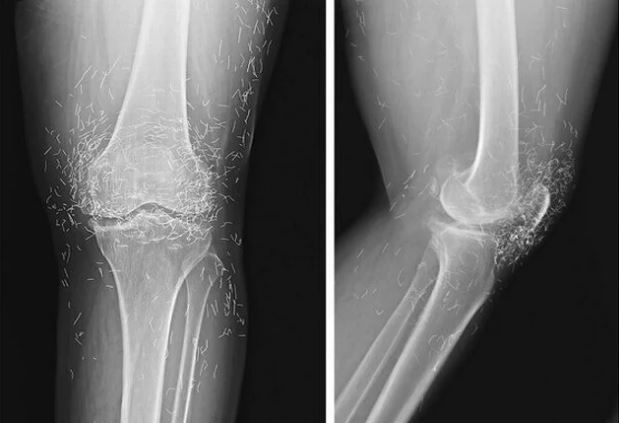

How Osteoarthritis is Treated

x-ray of knee joints

Credit: Pixabay

While the condition cannot be reversed, there are therapies and medications that help reduce pain and improve mobility.  For those with mild pain, Acetaminophen has been shown to help. Common pain relievers, like ibuprofen and naproxen sodium, also typically help relieve osteoarthritis pain. Those who suffer from the condition also benefit from physical and occupational therapy. A physical therapist can show you how to strengthen the muscles surrounding your joints, and an occupational therapist will teach you how to do everyday tasks without putting extra stress on your joints.

There are also various procedures that can help if the above treatments are not sufficient. For example, cortisone injections into the joint may potentially bring pain relief for a few weeks. Additionally, Injections of hyaluronic acid may also relieve pain by providing some cushioning in your knee. However, some research has suggested that this may simply be a placebo effect. They may also try realigning bones with a knee osteotomy or replace the joint with metal and plastic parts.